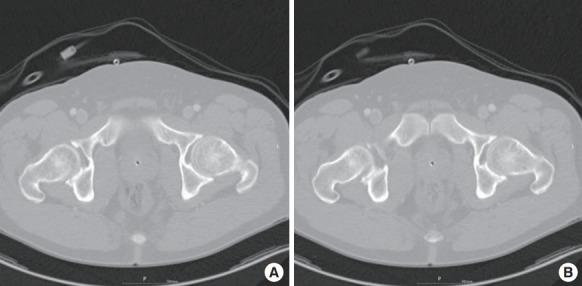

This research consisted of two studies. In first study, 100 females who visited the emergency department with gastroenteritis between 2007 and 2011 were included. In second study, 40 women who underwent IP-RAM flap in the same period were included. Using abdominal computed tomography, we measured the distance between xiphoid process and umbilicus, represented by value a, and the distance between umbilicus and symphysis pubis, represented by value b. Thus, the location of the umbilicus was represented by the ratio a/b. The data were analyzed using Pearson correlation test and paired t-test.

In study 1, the mean value of a/b was 1.07. Pearson correlation test revealed a significant correlation between age and a/b. In study 2, the mean value of a/b was 1.16 in preoperative measurements and 1.01 in postoperative measurements. The paired t-test showed a significant difference between preoperative and postoperative measurements, indicating cephalic migration of the umbilicus after surgery.

本研究包含两项。第一项研究纳入2007年至2011年间因肠胃炎就诊于急诊科的100名女性。第二项研究纳入同期接受IP-RAM瓣手术的40名女性。通过腹部计算机断层扫描,我们测量了剑突与肚脐之间的距离(用a值表示)以及肚脐与耻骨联合之间的距离(用b值表示)。因此,肚脐的位置用a/b比值表示。数据采用Pearson相关检验和配对t检验进行分析。

在研究1中,a/b的平均值为1.07。Pearson相关检验显示年龄与a/b之间存在显著相关性。在研究2中,术前测量a/b的平均值为1.16,术后测量为1.01。配对t检验显示术前和术后测量存在显著差异,表明术后肚脐向头侧移位。